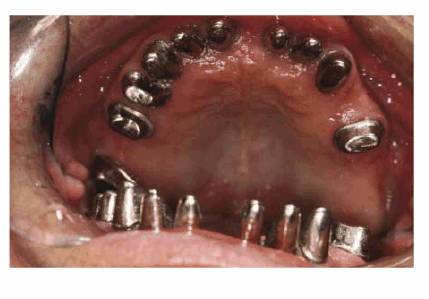

In instances where the patient has had posterior bite collapse and advanced

rehabilitation. Such a case is illustrated in Figures 23-19A, 23-19B, 23-19C, 23-19D, 23-19E, 23-19F and G, and 23-19H and I using interim bonding followed by a telescopic

Figure 23-19C: Following periodontal therapy and interim stabilization for 3 months, a maxillary telescopic prosthesis was constructed. The gold copings are seen here on the model.

Figure 23-19D: The superstructure was constructed in two sections using a semiprecision attachment.

Figure 23-19E: The gold copings are seen here cemented in the mouth with final cement. This permits the superstructure to be cemented with soft cement so that it can be easily removed in the event that repairs are necessary. A further advantage in using "individual" telescopic copings is that the patient will require only minimal treatment if there is a superstructure cement washout.

Figure 23-19F and G: The superstructure was first cemented with petrolatum and zinc oxide for 1 week to help fully seat the case.